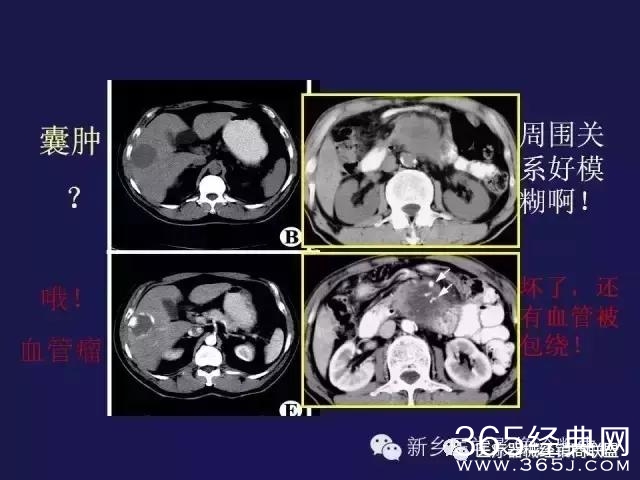

CT、MRI很难?NO,今日我们一起来学习一下如何读CT、MRI!

内行看门道: